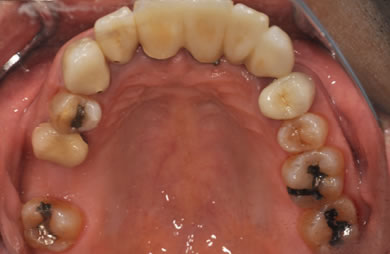

治療前

• 治療前